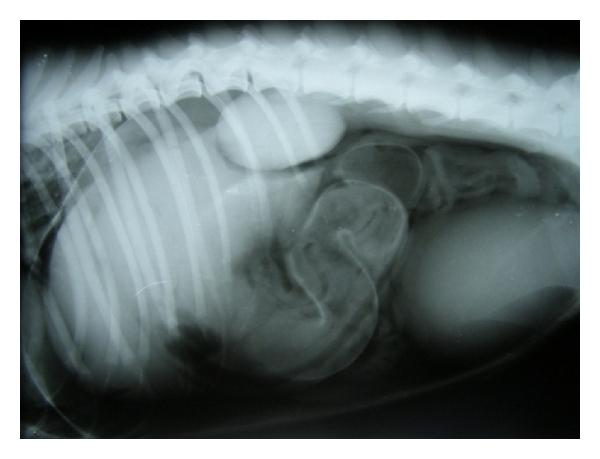

Hepatic disease is often treatable and has a predictable prognosis when a definitive diagnosis is made. The aim of clinicopathological evaluation of hepatobiliary affections is to identify and characterize hepatic damage and dysfunction, identify possible primary causes of secondary liver disease, differentiate causes of icterus, evaluate potential anaesthetic risks, assess prognosis and response to xenobiotics, and monitor response to therapy. This paper describes the different diagnostic methods and imaging techniques employed in diagnosis of hepatobiliary affections in dogs. Besides reviewing the significant clinical manifestations and imaging structural abnormalities in diagnostic approach to different hepatic affections, it also depicts radiographic, ultrasonographic, and wherever applicable, the laparoscopic characterization of different hepatic affections and target lesions encountered in clinical cases presented in the Teaching Veterinary Clinical Complex, COVAS, Palampur in the year 2007-2008.

肝病通常是可治疗的,一旦做出明确诊断,其预后是可预测的。肝胆疾病临床病理评估的目的是识别和描述肝损伤及功能障碍,确定继发性肝病可能的主要病因,鉴别黄疸的病因,评估潜在的麻醉风险,评估预后及对外源化学物质的反应,并监测治疗反应。本文描述了用于诊断犬肝胆疾病的不同诊断方法和成像技术。除了回顾不同肝病诊断方法中的重要临床表现和成像结构异常外,还描述了2007 - 2008年在帕兰普尔兽医临床综合教学中心(COVAS)出现的临床病例中不同肝病及目标病变的放射学、超声学特征,以及在适用情况下的腹腔镜特征。